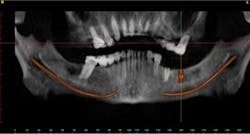

Case study A 58-year-old male with a noncontributory medical history presented to a private practice for a complete rehabilitation of his dentition due to years of bruxism and parafunction. (Fig. 1) After surgical and restorative consultations, a treatment plan was fabricated. The treatment plan included restoring his lost vertical dimension, restoring his natural dentition with porcelain-fused-to-metal full-coverage crowns, and replacing his lost posterior teeth with dental implants. After his vertical dimension was restored with an acrylic bite plate to a position harmonious with TMJ function, crown-lengthening surgery was performed. (Fig. 2)Fig. 2 Six weeks after, the teeth were temporized to develop soft tissue margins/interdental papillae. (Figs. 3 and 3a) The patient was kept in temporaries for three months, during which time an implant was placed in site No. 19. Both the natural dentition and the implant were completed at the same time, three months after implant placement. (Fig. 4) Because of the patient’s occlusal issues, the implant was screw-retained, and the patient was given a maxillary night guard. Three weeks after insertion, the patient presented with a loose abutment screw. The dentist tightened the screw and sent the patient home. This cycle was repeated two more times until the patient presented again with a loose crown, but this time, a fracture implant screw. The dentist attempted to remove the screw with a Cavitron and drilling the implant screw out to release preload, but to no avail. The case was then referred to my office for implant removal.